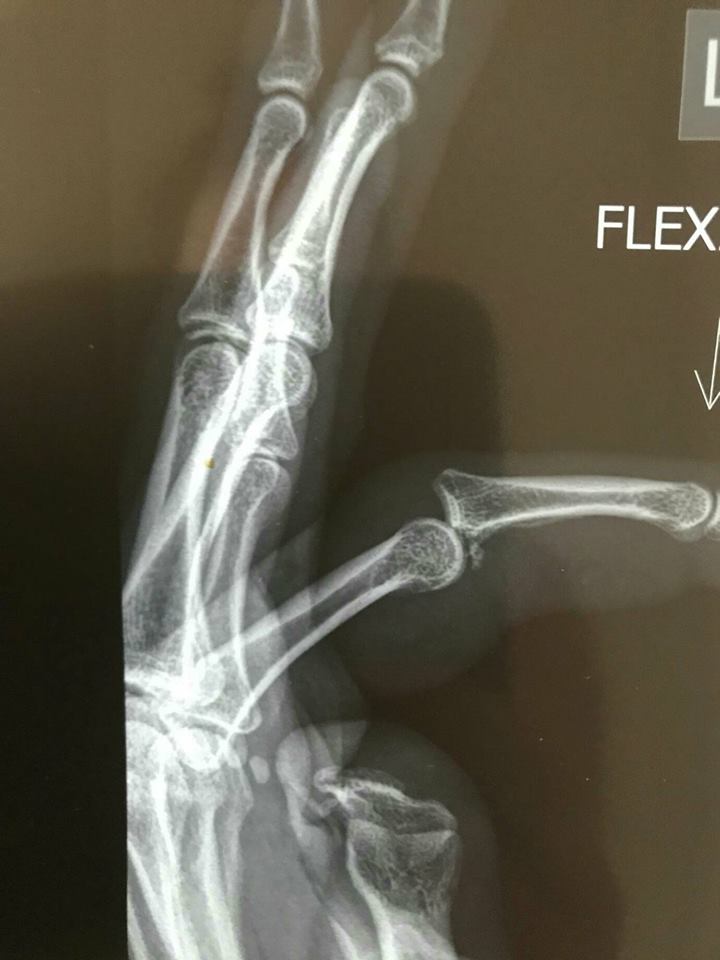

Scans, ultra sounds and X-rays revealed the extent of the damage but Hodges did not look at them, instead reading the injury summary.

Meeting with the specialist, Hodges finally looked at the actual scans to see what you now see, pictured.

"It was like: 'Holy $#!+' ... I couldn't believe it," she said.